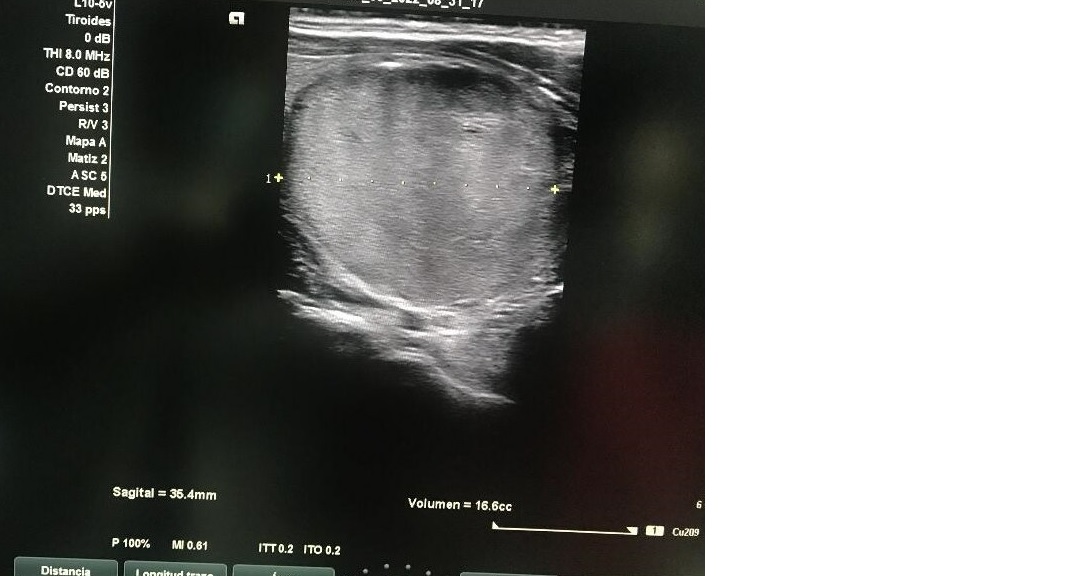

Ecografía tiroidea: Glándula tiroidea con ecoestructura homogénea en LTD con nódulo sólido en LTI con ocupación completa, hiperecogénico, bien delimitado con unas dimensiones de 3,5 x 3,5 x 4 con macrocalcificación en tercio superior con sombra acústica con vascularización de predominio periférico sin adenopatías cervicales.

Nodulo TIRADS 4 de 3,5 cm en LTI, sospecha de neoplasia folicular Bethesda IV.